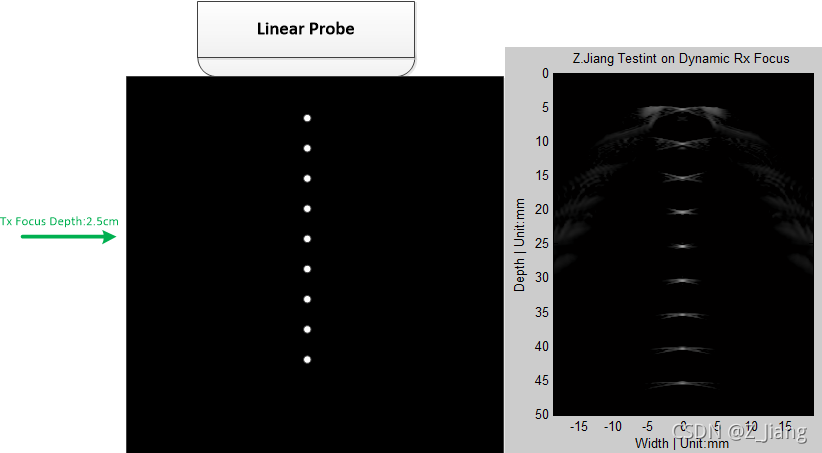

我们这次模拟的是一把128阵元,宽度为3.8厘米的线阵,7MHz的发射频率,中央正下放配置几个理想靶点(体积无限小,足够的强幅度,类似于数学中的delta function),对于接收到的信号,逐点计算延迟曲线进行接收聚焦,如下图所示

扫查示意图(左)模拟动态接收聚焦成像(右)

接收聚焦,孔径

在发射端我只给了一个延迟曲线和焦点,但接收我们可以根据深度变化,每个点的延迟曲线都可以单独计算,所以叫动态接收聚焦(Anyway,在工程上常常为了省资源,分成很多小段,一小段使用一组接收延迟曲线),由于越远的地方信号越弱,越近的地方信号越强(但杂波多),我们一般保持成像的深度与使用的接收阵元的个数(探头孔径)的比值为一个常数,即F#,焦径比,焦点与孔径大小的比值。

距离越远,成像需要开的孔径越大。大家还记得2019年与2021年EHT观察距离我们5500万光年的M87星系中心黑洞时,雷达的理论抽象孔径虽然达到了1.2万公里(即地球直径),但F#仍高达4.3X10^16,看不清是正常的,要知道我们上面成像仿真中F#=1,如下图

回到我们的超声成像,右侧图像基本反映了我们的实际扫查结构,但大家请留意:除了发射焦点深度(2.5cm)上聚焦比较理想,其它深度都比较差,我们预期远离焦点位置会差一些,但结果也太差了。主要原因是,我们还没有做遍迹Apodization;